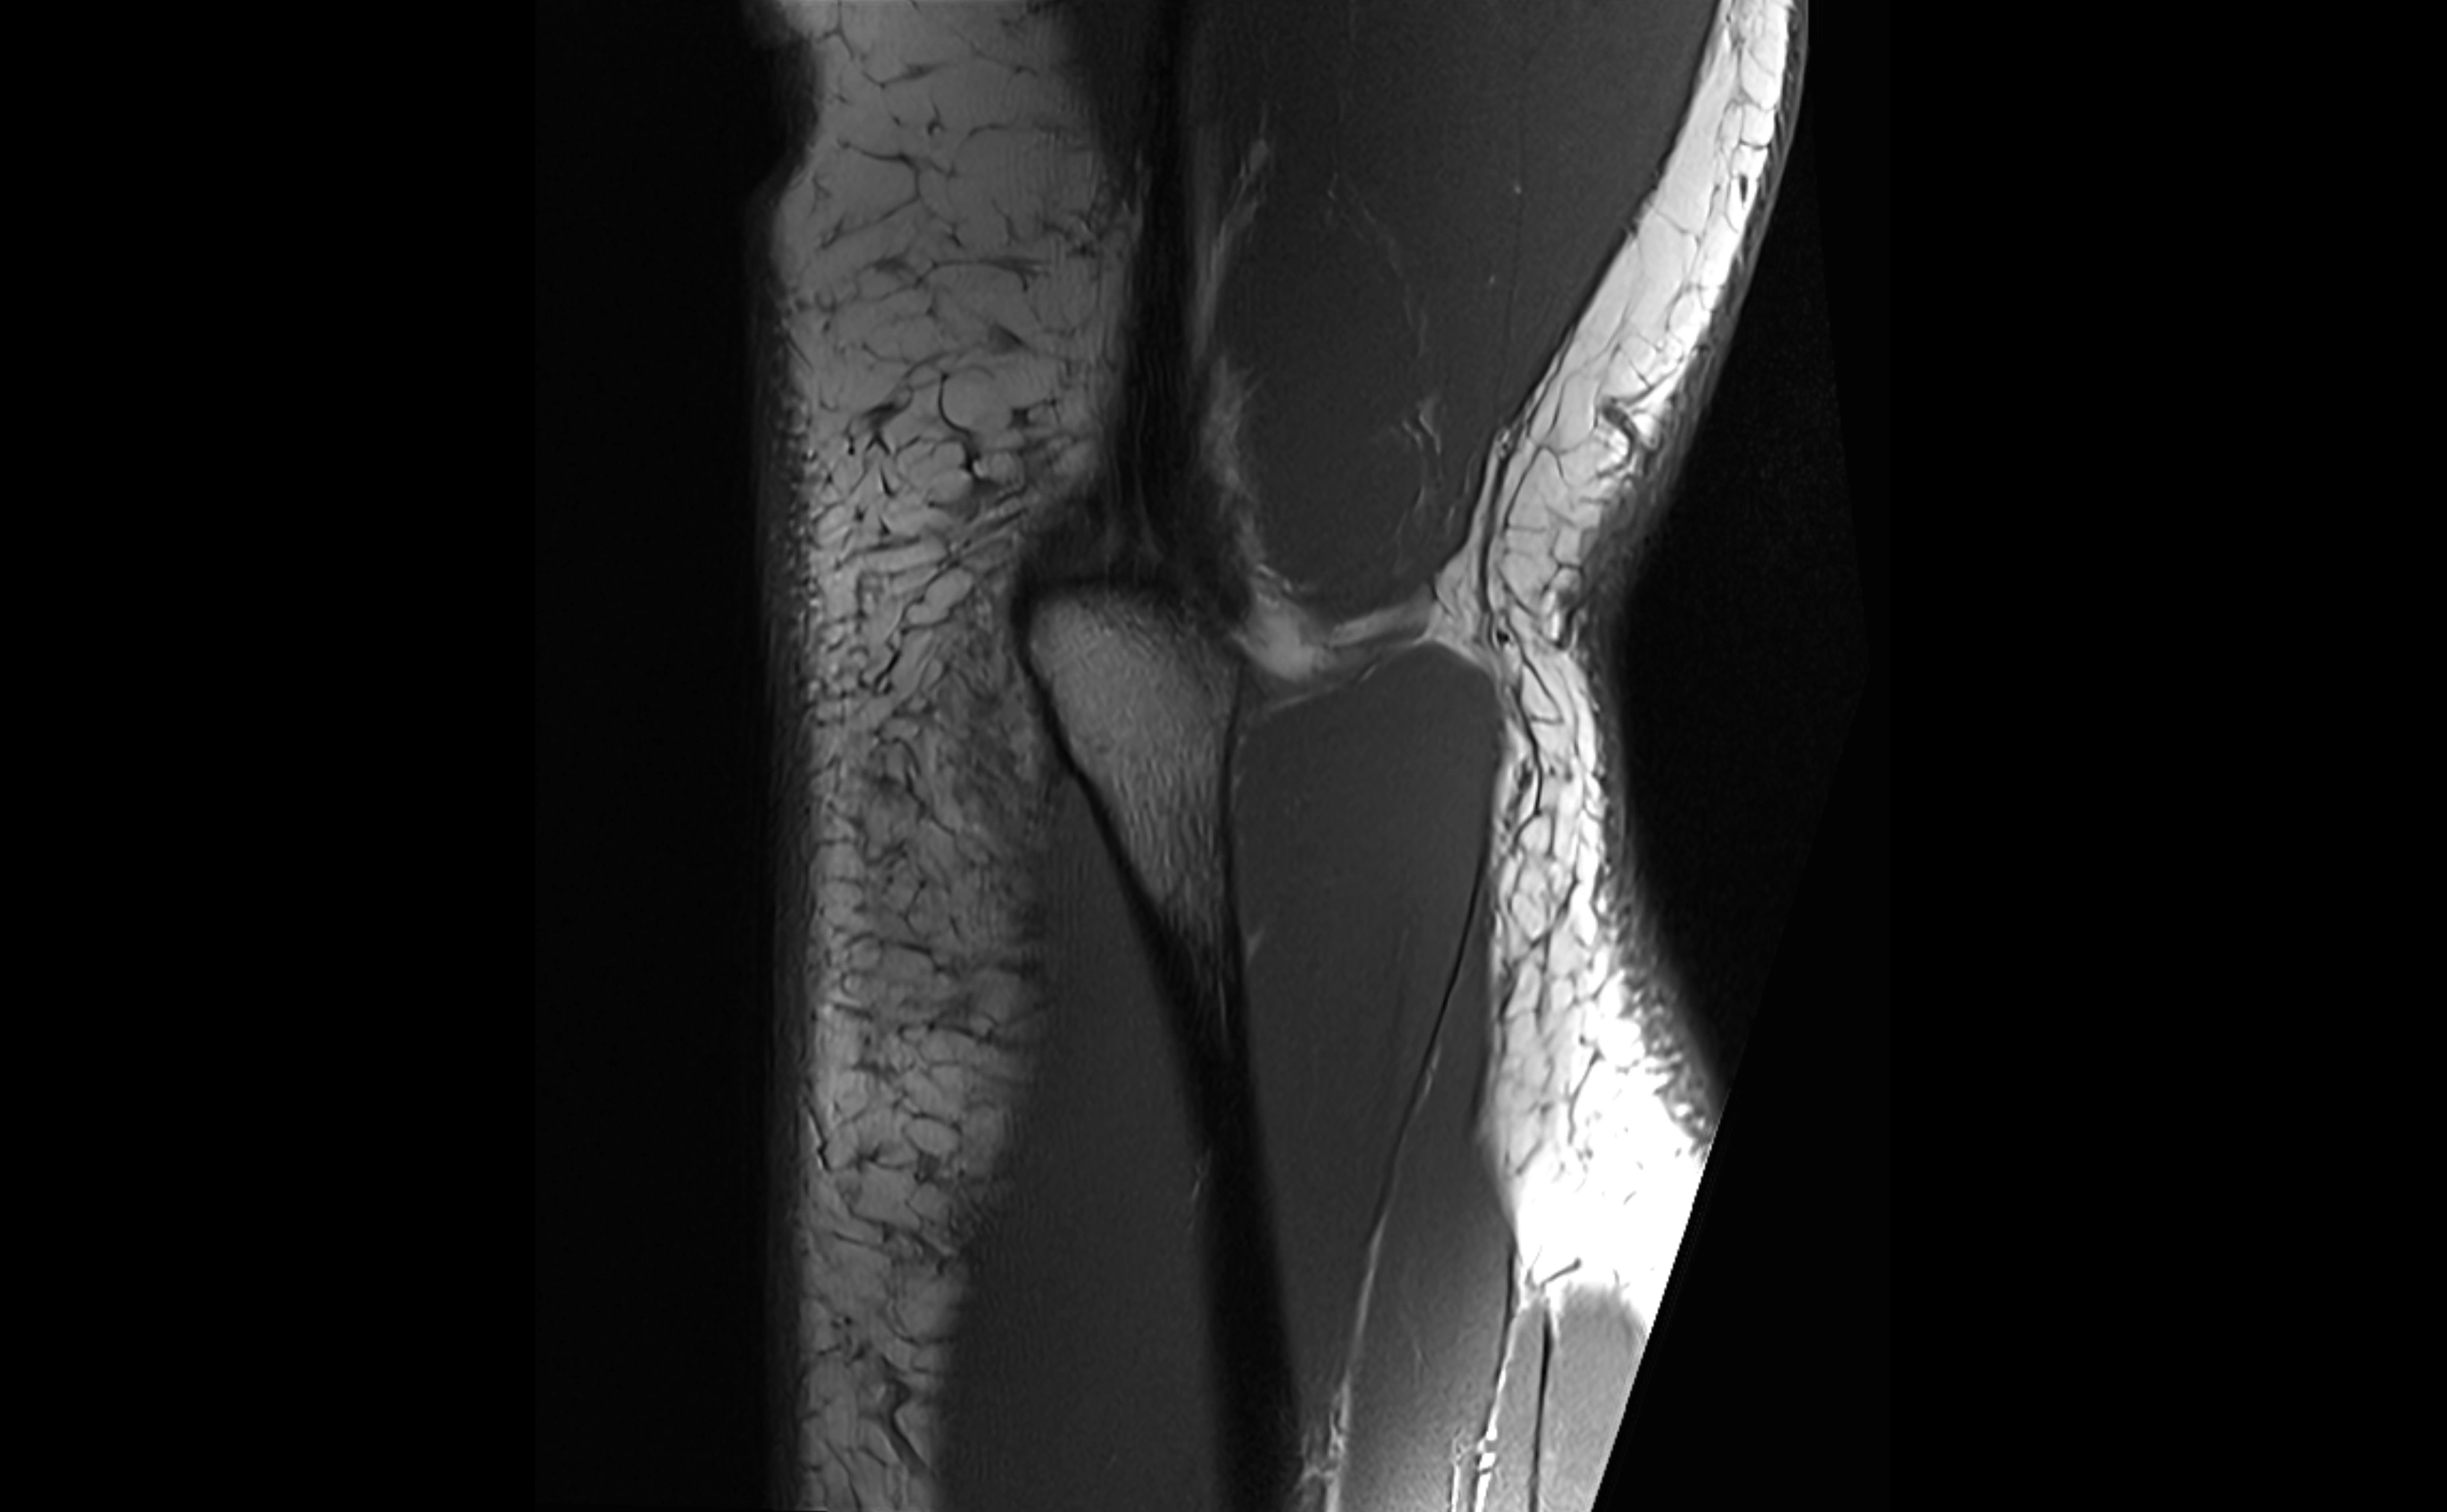

MRI images

image